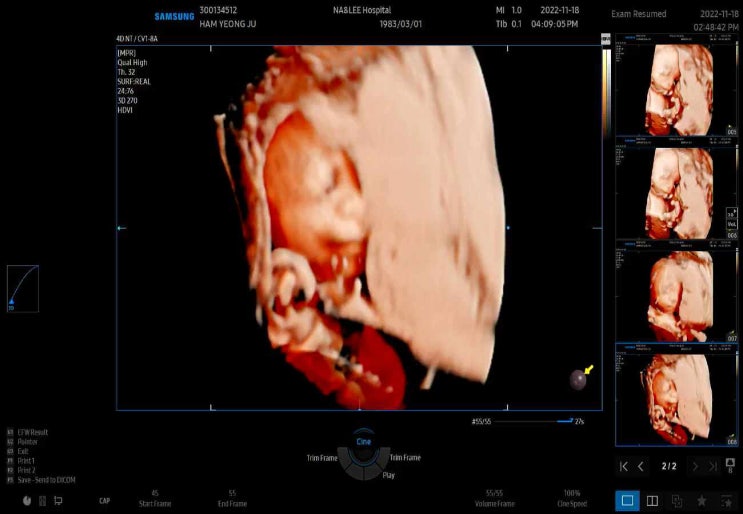

:) 우리애들 :D

2025.03.15

요즘 우리애들. 예나언니가 요즘들어 하트를 이뻐하기 시작함. 왜?? ㅋㅋㅋㅋㅋㅋ 예나방은 반려동물 금지...